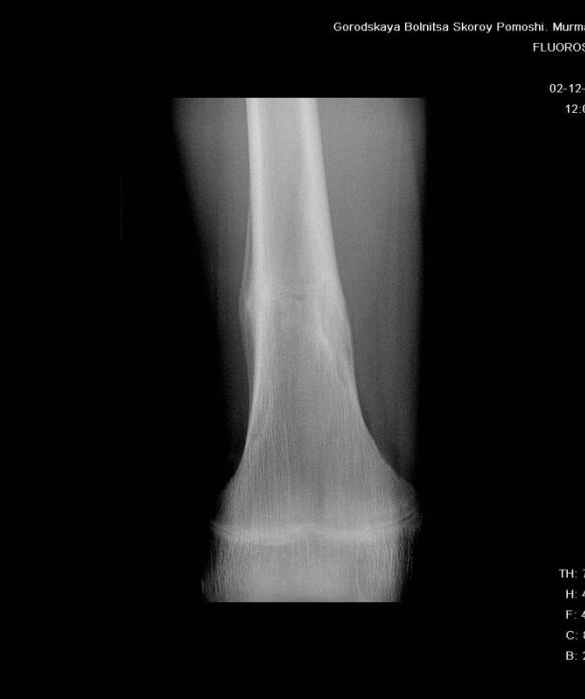

Здравствуйте, уважаемые коллеги!Представляю вашему вниманию интересный случай и пока что непонятный для меня в диагностическом плане. На днях в наше отделение (детской ортопедии и травматологии) поступил 13-летний мальчик по направлению из поликлиники с диагнозом: остеома нижней трети правого бедра.

Анамнез практически никакой: в следствие травмы (растяжение связок коленного сустава) от 07.11.2004 выполнены Rg-граммы в травмпункте и обнаружено опухолевидное образование. Первичные Rg-граммы я не публикую, так как они заметно худшего качества, да и динамики за прошедшие три недели не отражают. Болевой синдром купирован в течение трёх дней. В настоящий момент мальчика ничего не беспокоит. Ходьба не нарушена, опухоль пальпируется с трудом по задней поверхности в н\3 правого бедра, пальпация безболезненна, объем движений в суставах правой нижней конечности полный и симметричный. Кожа над опухолью не изменена.В нашей клинике проведено дополнительное обследование: общие анализы крови и мочи, биохимия крови без особенностей. Выполнены Rg-граммы на цифровом Siemens обычные и продольные томограммы срезами 3-5 мм, а также компьютерная томография поперечными срезами по 5 мм. Прошу обратить внимание, что на приведённых томограммах видны две полости 10х15 мм и 15х60 мм. Также имеются два опухолевидных образований наслаивающихся друг на друга: уплощённое и вытянутое 10х100 мм и элипсовидной формы 15х30 мм. Это хорошо заметно на фото a_1.jpg c_1.jpg и d_1.jpg. Плотность внутри полостей 125% от плотности костномозгового канала, плотность наружного опухолевидного образования 55% от плотности кортикального слоя. Также отмечается линия перелома по центру наружного опухолевидного образования.Исходя из полученных данных мнения в плане диагноза несколько разделились от 1)сочетания кортикальной фиброзной дисплазии и латентно протекавшего маршевого перелома н\3 правого бедра до 2)остеосаркомы. В отношении первого варианта не сходится отсутствие клиники при переломе такой крупной кости как бедро, второй вариант вообще оставлю без комментария, ибо некомпетентен. Хотелось бы услышать мнения коллег, с удовольствием ознакомлюсь с любыми предположениями и замечаниями.С уважением, Александр Е. КлоковОтделение детской ортопедии и травматологииБСМП г. Мурманска.